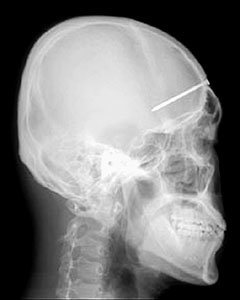

20대 남자가 5년 넘게 머리에 길이 5cm가량의 대못이 박힌 상태로 살아오다 3일 서울아산병원에서 못 제거 수술을 받았다.

또 이마 한 곳이 부풀어 오르고 염증이 생기기도 하자 개인병원을 찾아 X선 촬영을 했다. 그 결과 두개골에 길이 5cm가량 되는 대못이 박혀 있다는 놀라운 사실을 알아냈다.

가족들은 물론 한 씨 자신도 못이 언제 박혔는지 전혀 알지 못한다. 다만 “5년 전 이마에 기와 조각이 박히는 사고가 있었을 때 박힌 것 같다”고 짐작할 뿐이다.

다행히 못은 뇌의 민감한 부위를 절묘하게 피해 박힌 상태였다. 수술은 성공적으로 끝났으며 한 씨는 현재 일반 병동에서 치료를 받고 있다.